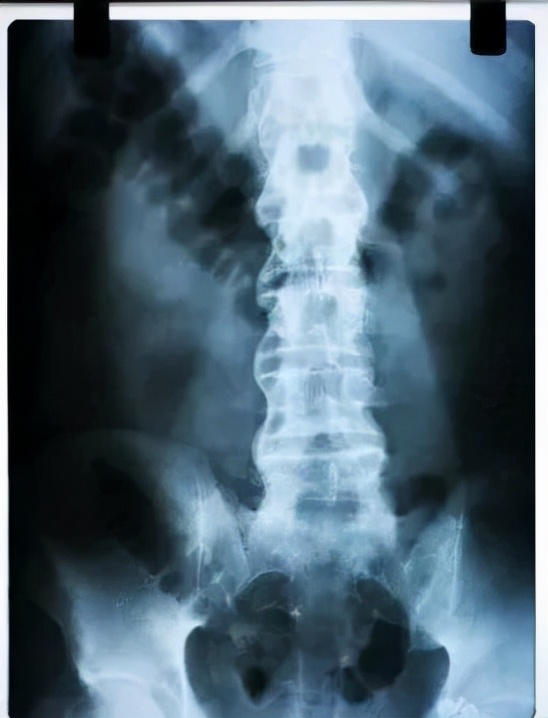

人类在20世纪30年代才认识到,几乎所有强直性脊柱炎患者都存在X线骶髂关节炎,从此,X线骶髂关节炎成为该病诊断的必要条件。

但后来发现部分患者X光检查但却没发现骶髂关节破坏,但在磁共振(MR)下却能看到活动性炎症征象。